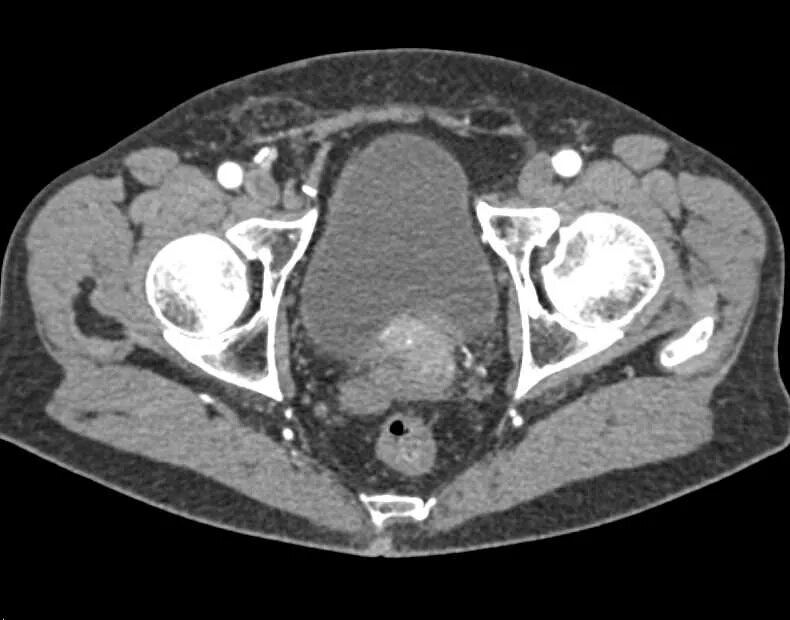

Кт мочевыводящих путей